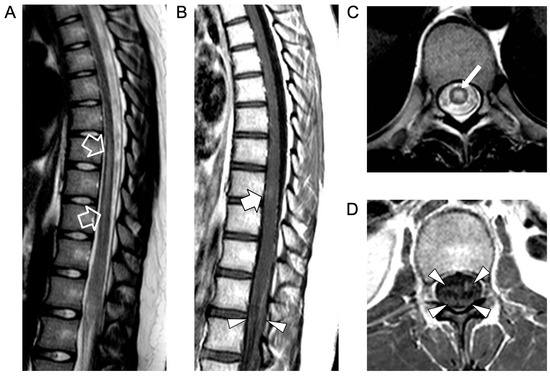

The electrophysiological study showed a low amplitude of somatosensory evoked potentials (SSEPs) in the lower limbs with the absence of F wave. Empirical therapy with ceftriaxone twice daily, 750 g acyclovir three times a day, 2 g/kg immunoglobulins, and 1 g/dose methylprednisolone (×4 bolus) was administered with a decrease in lumbar pain but no improvement in the strength of the lower limbs. A second spinal MRI, performed 5 days later, showed caudal extension of the acute transverse myelitis involving the conus medullaris, with more pronounced nerve root contrast enhancement, associated with an anterior spinal cord infarction (Figure 2)

Figure 2.

Contrast-enhanced spinal MRI performed 5 days after the clinical onset. Sagittal T2-weighted (A) and 3D driven equilibrium (DRIVE) (B,C) images; axial T2-weighted (D,E) images and diffusion-weighted image (F) with corresponding ADC map (G). There is a caudal extension of the T2 signal alterations involving the conus medullaris (empty arrows). Bilateral, symmetrical circular foci of high T2 signal are visible in the anterior horns of the spinal cord (i.e., owl-eyes sign) in the dorsal segment with a cranial extension to the D1 level (thin arrows). The spinal cord lesions are characterized by high signal on diffusion-weighted images with reduced ADC values (arrowheads) in keeping with a spinal cord infarction. In addition, there are several non-enhancing intradural extramedullary lesions along the cauda equina nerve roots and conus medullaris surface (dashed arrows).

An intradural extramedullary lobulated lesion was also noted at the level of the conus medullaris, with several similar small nodular lesions spreading along the cauda equina nerve roots and conus medullaris surface (Figure 2). A brain MRI demonstrated small subcortical gliotic changes in the right temporal lobe that remained stable in follow-up studies. Chest computed tomography (CT) and whole-body MRI were negative, as well as spinal digital subtraction angiography. A new CSF examination was performed: no atypical cells were detected but immunochemical tests showed barrier damage in the absence of oligoclonal bands. New microbiological tests and PCR on CSF and blood excluded some infective etiologies, in particular the presence of Cryptococcus, Aspergillus, Mycobacterium tuberculosis, Borrelia, Yersinia, Toxoplasma, and Bartonella. Antimicrobial therapy was shifted to 600 mg teicoplanin per day, subsequently substituted with 3 g ampicillin four times a day. For the suspicion of neoplastic disease, a biopsy of the extramedullary lesion was performed, revealing an ischemic lesion with perivascular inflammatory infiltrates and phagocytosis of uncertain significance, suggestive of an unspecified infective lesion. While waiting for the histological analysis, a second infusion of immunoglobulin, oral cyclophosphamide, and steroids was started for the suspicion of SLE-related transverse myelitis. An immediate postoperative spinal MRI performed 3 weeks after the onset revealed complete removal of the intradural extramedullary mass, while the spinal cord lesion and nerve root involvement were stable. The clinical picture worsened with progressive paraplegia and anesthesia of the lower limbs, urinary incontinence, and deterioration of neurophysiological findings. During the following weeks, plasmapheresis, cyclophosphamide, and immunoglobulin were administered and ampicillin was continued. Spinal MRI performed 6 weeks after clinical onset and showed a new acute ischemic lesion involving the inferior dorsal spinal cord and conus medullaris and additional small nodular lesions along the conus medullaris surface (Figure 3).